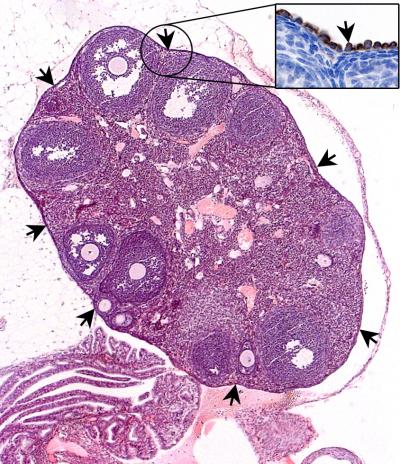

Stem cells exist in many tissues, and are responsible for ensuring healthy tissue function, by giving rise to new cells to replenish those lost during normal wear and tear. However, the existence of stem cells and their identity in the ovary has remained elusive. The ovary is covered by a single layer of epithelial cells (Figure 1) and much of the research in the field been dedicated to understand their stem cell biology, as the majority of human ovarian cancers are believed by scientists to originate from the carcinogenic transformation of a single ovary epithelial cell.

A*STAR's IMB has now determined that Lgr5-expressing ovary epithelial cells have a long lifespan, and that they continuously self-renew by producing new cells to replace those lost over the reproductive lifetime of the organism. The team is now studying the mechanisms of how Lgr5-expressing stem cells regenerate in normal tissue. The regenerative ability of Lgr5-expressing stem cells makes them potentially useful for therapies that require tissue repair or replacement, such as through gene therapy to tackle ovary defects.

By using Lgr-5 as a biomarker to isolate and purify normal ovary stem cells and ovarian cancer stem cells, scientists can now compare normal and cancerous cells to identify differences between them. Such differences may then represent new therapeutic targets for ovarian cancer treatment.